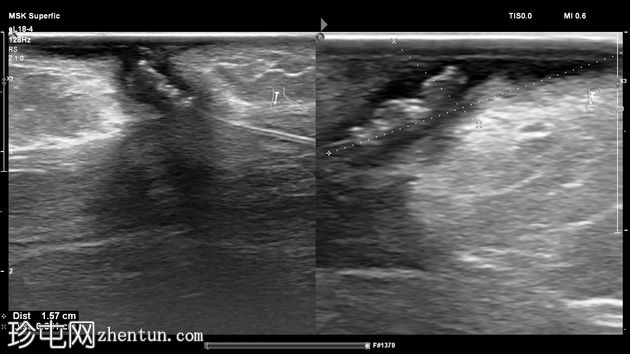

超声检查

纵位

横位

左足跟皮下组织内可见一管状高回声物质,呈串珠状,与手术缝线相符,周围环绕着低回声积液。与缝线相连的是一根细细的、呈轨道状的高回声合成单丝,它穿过跟腱呈弧形走行,该缝线为不可吸收缝线。